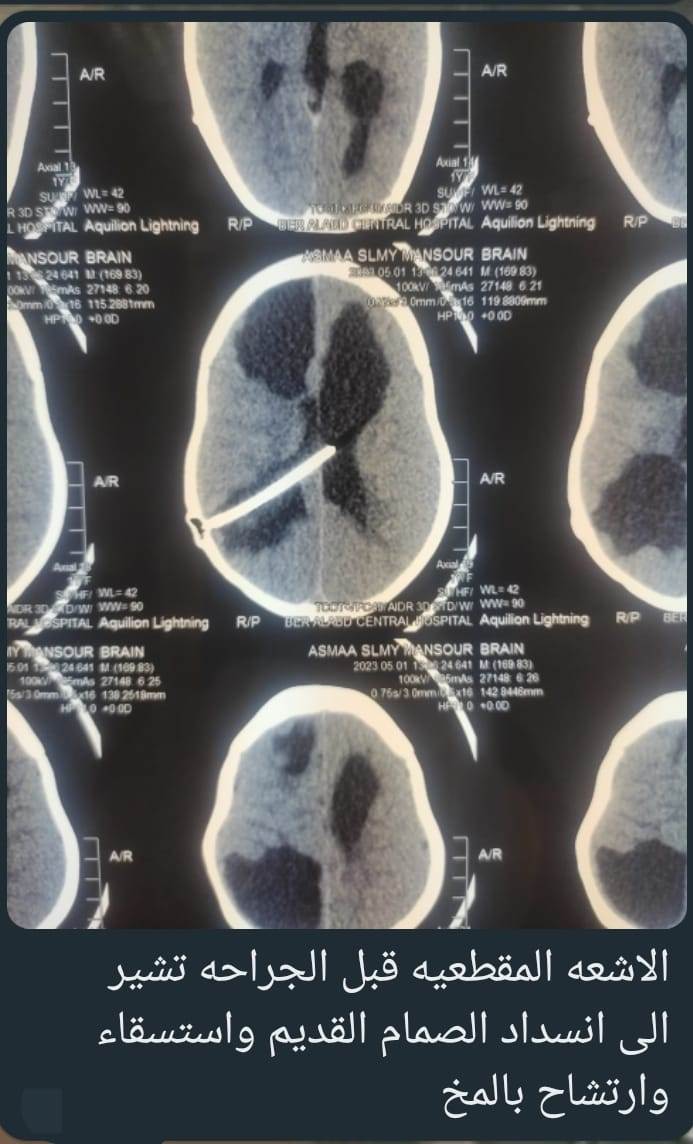

وأعلن الدكتور تامر حمدى أحمد مدير عام المستشفى (في بيان) عن قيام الدكتور محمود محمد متولى مدرس مساعد جراحه المخ والأعصاب بجامعه الزقازيق والدكتور محمود مصطفى مدرس التخدير في قصر العيني بجامعة القاهرة باجراء جراحة لطفلة عمرها عامين كانت تعانى من استسقاء بالمخ وتدهور بدرجة الوعي وقىء بسبب تعطل الصمام المنظم للسائل الشوكي.. حيث تم اجراء جراحة عاجلة لاصلاح الصمام واستبداله بصمام آخر جديد، وأصبحت المريضة بعد الجراحة في حالة صحية جيدة وتحسن فوري بشكل ملحوظ بعد الجراحة، وأصبحت فى كامل درجة الوعى وتوقف القىء وبداية الرضاعة والتغذية بالفم بشكل اعتيادي.